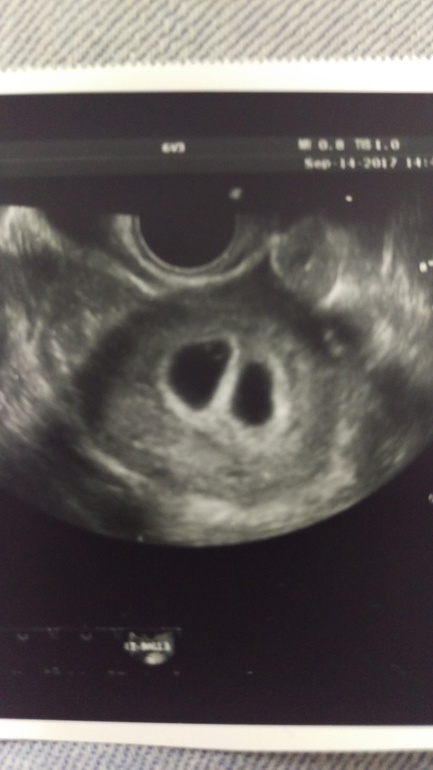

Вчера было первое узи на 22 дпп, как я переживала.... начала рыдать как только на кресло залезла, Ре отругала меня, и потом говорит что у нас двойня и тут меня накрыла вторая волна истерики, и я уже не могу остановиться (может так гормоны влияют не знаю)

В полости матки два плодный яйца вроде по 16мм в них по жм и эмбриону и оба сб+ (первый ктр 3,5 мм, второй ктр 3,0 мм)